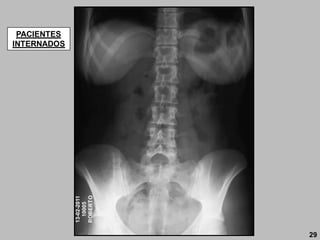

PACIENTES

INTERNADOS

29